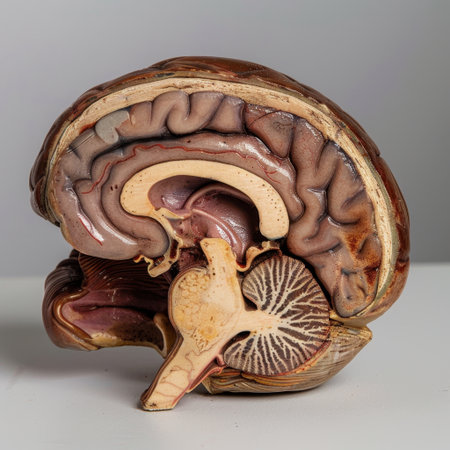

This detailed cross-section of the human brain illustrates its anatomical features, making it ideal for educational purposes in neuroscience and medicine.

This close-up photo captures the intricate details and structures of a human brain, Cross-sectional image of a human brain, AI Generated